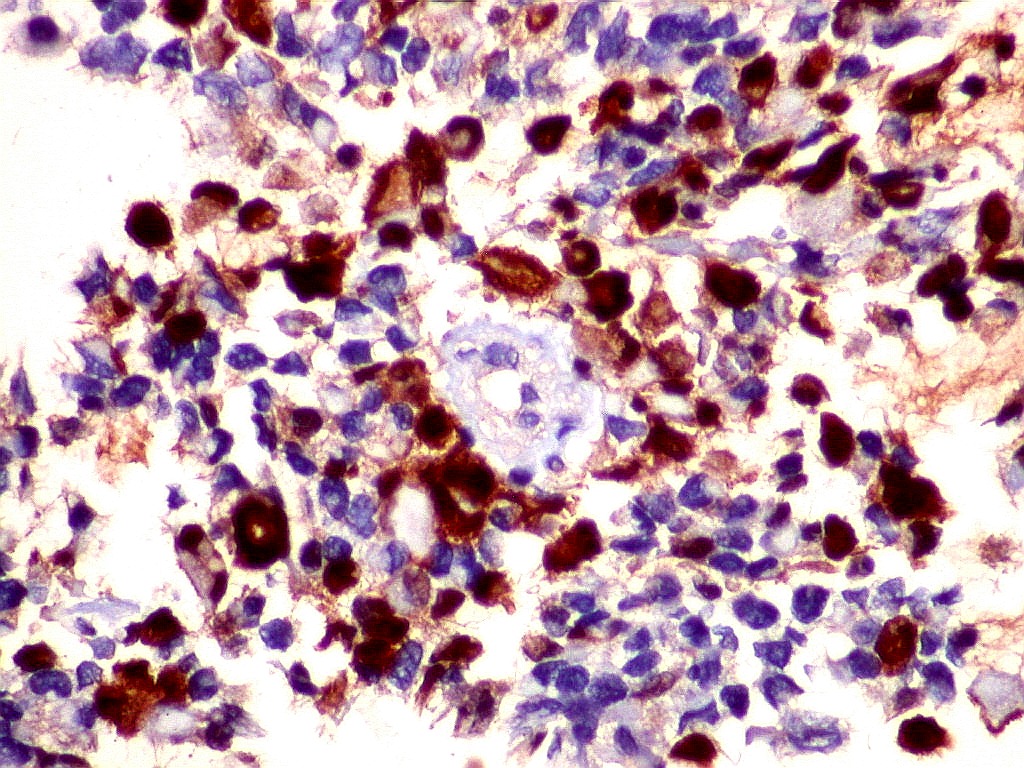

MAP2.   Microtubular associated protein,  marcador de diferenciação  neuronal. Universalmente positivo nas células deste ATRT.  Folículo linfóide  negativo (controle  interno).  Marcação é citoplasmática, na periferia do citoplasma.  Corpúsculo rabdóide negativo.  Para mais sobre MAP2, clique.